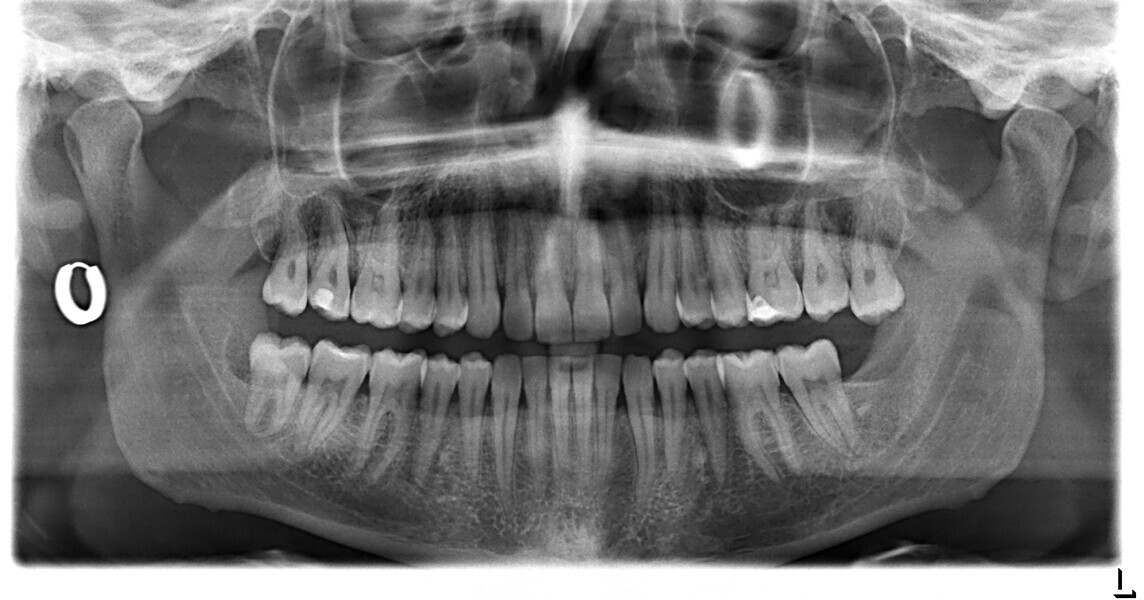

A 37-year-old male patient presented with the chief need for re establishing anterior alignment in both arches. Facial analysis showed a short face with a flat profile but proper chin projection (Figs. 9–12), and clinical examination revealed a skeletal Class I (ANB = 0.89°) and dental Class I malocclusion with severe deep bite (almost 100%), a deep curve of Spee, normal maxillary central incisor torque (Ui–FH = 110°), mild maxillary crowding and moderate mandibular crowding (Figs. 13–18). The deep bite components were represented in this patient by the severe skeletal condition of hypo divergent pattern (FMA = 14.24°) with normal maxillary and mandibular incisor inclination and decreased gonial angle (110.46°). Analysis of the cephalometric radiograph indicated a reduced lower anterior facial height, combined with a hypo-divergent pattern (Fig. 19). The only treatment option suggested was orthodontic treatment with aligners for deep bite correction with all the features described (bite ramps, pressure area, 3D curve of Spee levelling, Class II elastics and heavy occlusal contacts).

Fig. 13

Fig. 19